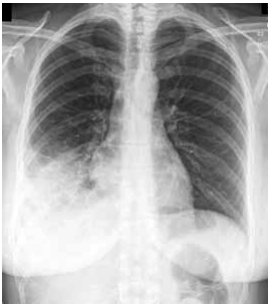

Homem, 70 anos, hipertenso de longa data, apresenta tosse com expectoração abundante e amarelada, e febre de 38 graus há 4 dias. Faz uso de anlodipina e enalapril e não teve internação hospitalar recente. Exame físico: regular estado geral, consciente e orientado, taquipneico (FR = 32 ipm), pressão arterial = 80x50 mmHg, frequência cardíaca = 118 bpm, SpO2 = 91% em ar ambiente. A ausculta pulmonar revela estertores crepitantes em base do hemitórax direito, com alguns roncos de transmissão.

A radiografia de tórax está ilustrada a seguir.